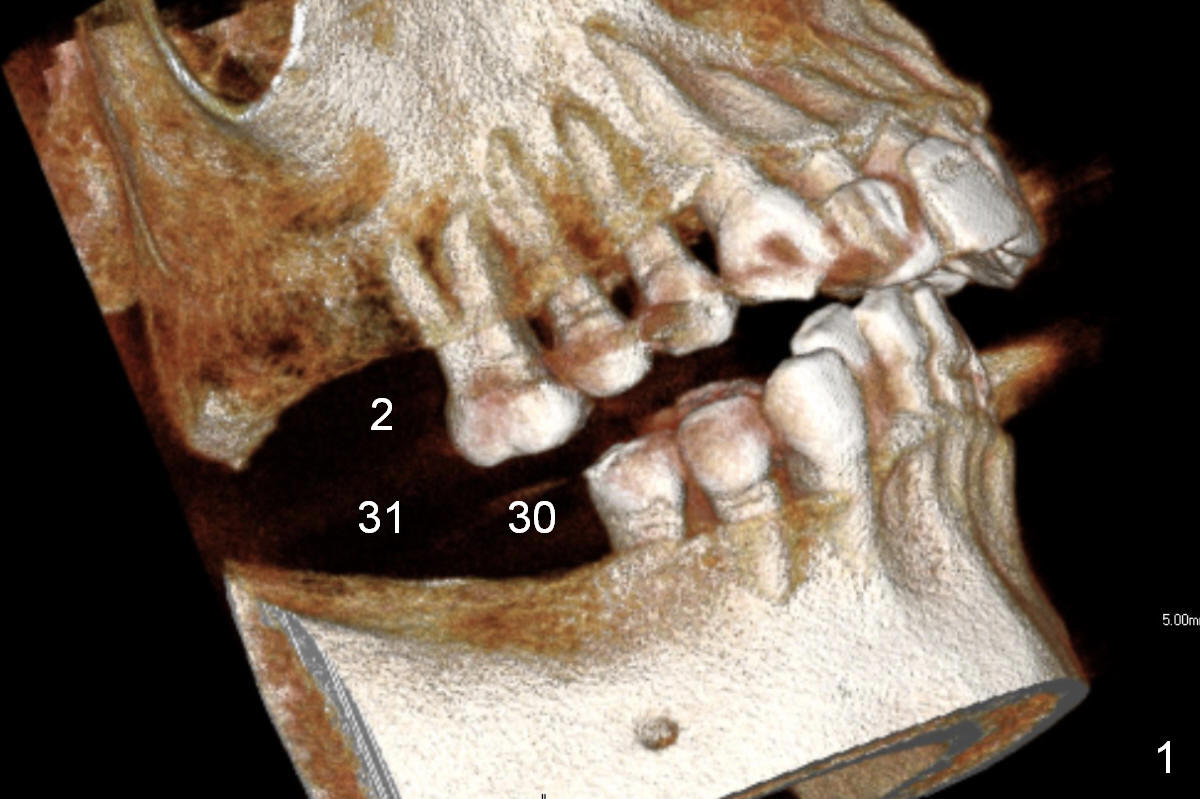

On the other hand, her occlusion is out of order. The teeth #2,14,15,30 and 31 are missing with #3 supraeruption and deep anterior overbite and overjet (Fig.1,2). This may lead to TMD. Alginate impression will be taken for fabrication of night guard or occlusal guard to raise vertical height. If this helps, implants are placed (Fig.3-6), followed by limited or comprehensive ortho to intrude #3, to permanently change her occlusion.